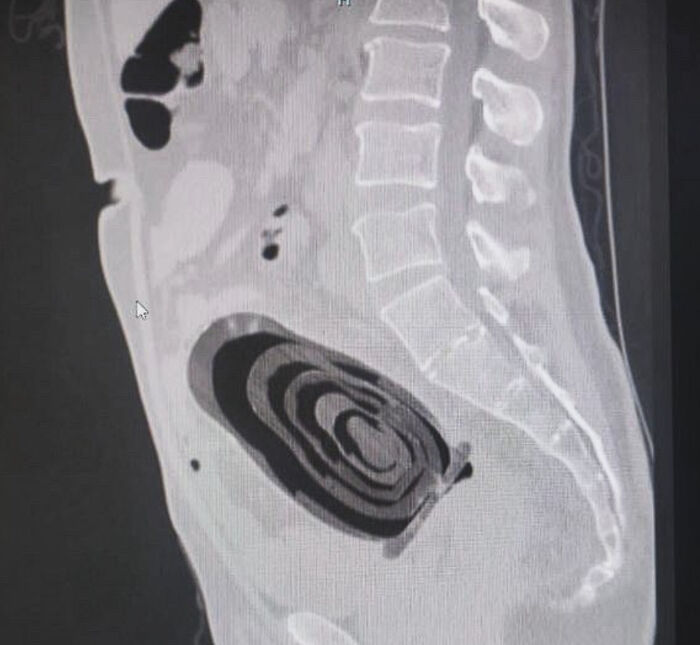

CT Scan Of A 13 Year Old From Gaza